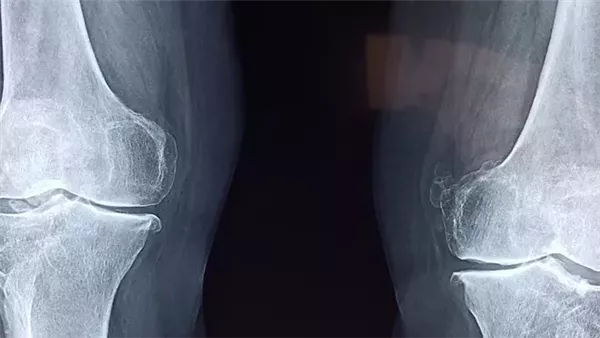

شهد القطاع الطبي إنجازًا علميًا لافتًا في الصين بعد إعلان باحثين من جامعة تشجيانغ عن تطوير مادة جديدة أُطلق عليها اسم غراء العظام Bone O2، يمكنها إصلاح الكسور المعقدة في غضون 3 دقائق فقط. الابتكار، الذي قاده الجراح لين شيانفينغ من مستشفى سير رون رون شو، يُتوقع أن يُحدث نقلة نوعية في علاج إصابات العظام ويقلل من الحاجة إلى التدخلات الجراحية التقليدية، وذلك وفقًا لما نشر في ماركا الإسبانية.

وأوضح شيانفينج، أن هذه المادة المستوحاة من قوة التصاق المحار بالصخور، أثبتت فعاليتها العالية حتى في وجود كميات كبيرة من الدم، حيث تتميز بقدرتها على تثبيت الكسور دون الحاجة إلى صفائح أو براغٍ معدنية. والأهم من ذلك، أن الجسم يمتصها مع مرور الوقت، ما يلغي الحاجة إلى إجراء عملية جراحية ثانية لإزالة الغرسات، ويقلل من احتمالية رفض الجسم للأجسام الغريبة.

وآلية التطبيق بسيطة، إذ يُستخدم غراء العظام عبر شق جراحي صغير، ما يقلل من وقت التعرض في غرفة العمليات ويخفض خطر العدوى، فضلًا عن تسريع فترة التعافي، وتشير نتائج الاختبارات الأولية إلى أن المادة قد تكون بديلًا قويًا للغرسات المعدنية التقليدية، إلا أن موعد طرحها للاستخدام التجاري الواسع لم يُحدد بعد.